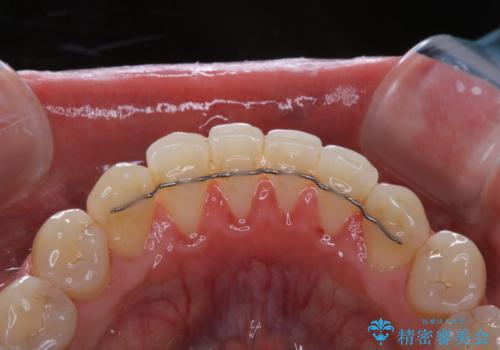

全体的にプラークや歯石が付着していて、歯肉炎が見られました。

状態に合った専門的な器具を使用して、歯質や歯肉へのダメージを抑えながらPMTC(自費クリーニング)60分コースを行いました。矯正治療後の保定装置がワイヤーの場合、フロス・糸ようじが通せないこと、歯ブラシがしずらいことなどにより、歯石プラークなどが付着しやすくなります。そのため専門的な器具による細かいケアを行うことがとても大切です。